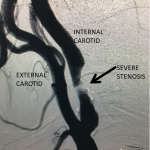

Figure 3.

Catheter angiography prior to angioplasty revealed critical stenosis (Figure 2). Angioplasty was therefore performed under local anesthesia with an embolic protection device deployed to catch any dislodged debris (Figure 3). After angioplasty, a stent was opened across the lesion to maintain long-term patency (Figure 4). Post-stent angiography showed smooth dilatation of the lesion. The patient’s aphasia continued to improve at his 6-week follow-up visit and duplex revealed no significant stenosis through the stent.